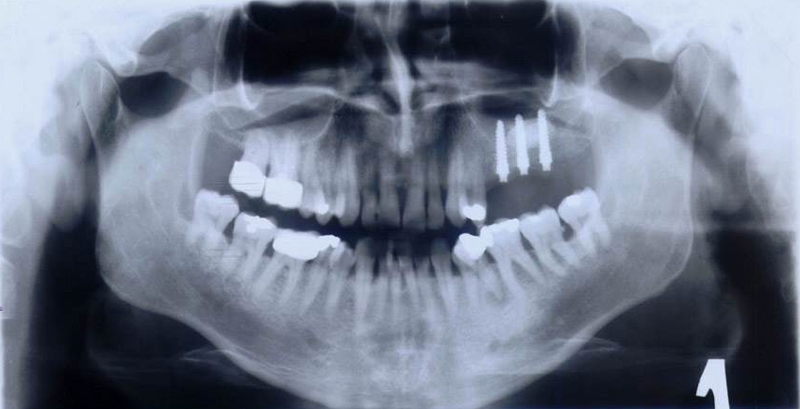

Novinkou v augmentačních metodách, kterou jako první v České republice používáme v našem zařízení je ultrazvuková metoda pomocí polylaktidové membrány - SonicWeld Rx®, kterou zavedl do implantologie v roce 2009 Dr. Dr. G.Iglhaut (Memmingen, Německo).

Jedná se o augmentační metodu při dostavbách kosti a defektech kosti horní a dolní čelisti.

SonicWeld Rx